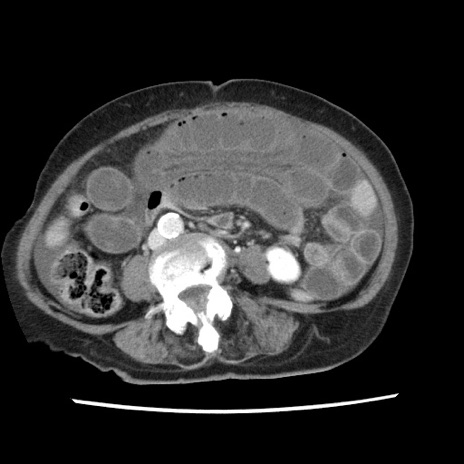

症例1(横断像)

【症例】80歳代女性

【主訴】腹痛

【現病歴】8時間前から腹痛あり来院。

【既往歴】糖尿病、脂質異常症、子宮体癌にて子宮全摘術

【身体所見】意識清明・会話良好だが腹痛で苦悶様、全腹部にわたって反跳痛と圧痛あり

【データ】WBC 13600、CRP 0.14、LDH 224、CK 90